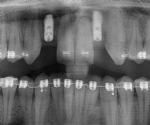

Kombination mit Implantaten – Brücken – Kronen

Die Versorgung stärker zerstörter Zähne oder von Zahnlücken durch den Zahnarzt mit Kronen und Brücken oder Implantaten führt oft zu wesentlich schöneren Ergebnissen, wenn die vorhanden Zähne, etwa Pfeilerzähne für Brücken oder Zähne neben geplanten Implantaten, vorher kieferorthopädisch eingestellt werden.

Verankerung – Miniimplantat

Im Rahmen der Behandlungsplanung wird die Richtung der Zahnbewegungen festgelegt. Um bestimmte Zahnbewegungen ohne unerwünschte Nebenwirkungen durchführen zu können, sind manchmal Verankerungen sinnvoll, die unabhängig von den Zähnen sind.

Besonders elegant ist dabei die Anbringung kleiner Pins neben den Zähnen oder im Bereich des Gaumens. Diese so genannten Mini-Implantate verankern sich zahnunabhängig im Kiefer und erlauben zielgerichtete Bewegungen. Die Behandlungszeit verkürzt sich entsprechend.